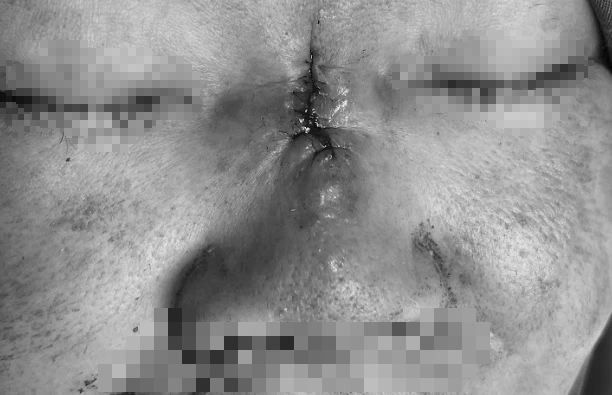

Hai tuần sau, vùng mũi chuyển màu đen tím, lan rộng. Khi quay lại yêu cầu xử lý, cơ sở đã biến mất. Chị K. rơi vào trạng thái hoang mang, sợ hãi đến mức không dám trình báo cơ quan chức năng.

Chỉ đến khi vùng mũi đau nhức dữ dội, chảy dịch và bắt đầu hoại tử lan rộng, chị mới gắng gượng tìm đến Bệnh viện JW Hàn Quốc để chữa trị.

Mũi hoại tử, sưng tấy sau nâng mũi đổi vận

Ngày 15.10, tiến sĩ – bác sĩ Nguyễn Phan Tú Dung, Giám đốc chuyên môn Bệnh viện JW Hàn Quốc cho biết, vùng da dọc sống mũi viêm đỏ lan tỏa, phù nề và xuất hiện ổ hoại tử trung tâm màu đen, kèm thâm nhiễm mô xung quanh. Đây là dấu hiệu điển hình của thiếu máu cục bộ mô mũi do tắc mạch hoặc nhiễm trùng hoại tử mô mềm. Biến chứng này là hậu quả của việc luồn chỉ không rõ nguồn gốc, cộng với việc bơm chất lạ trôi nổi.